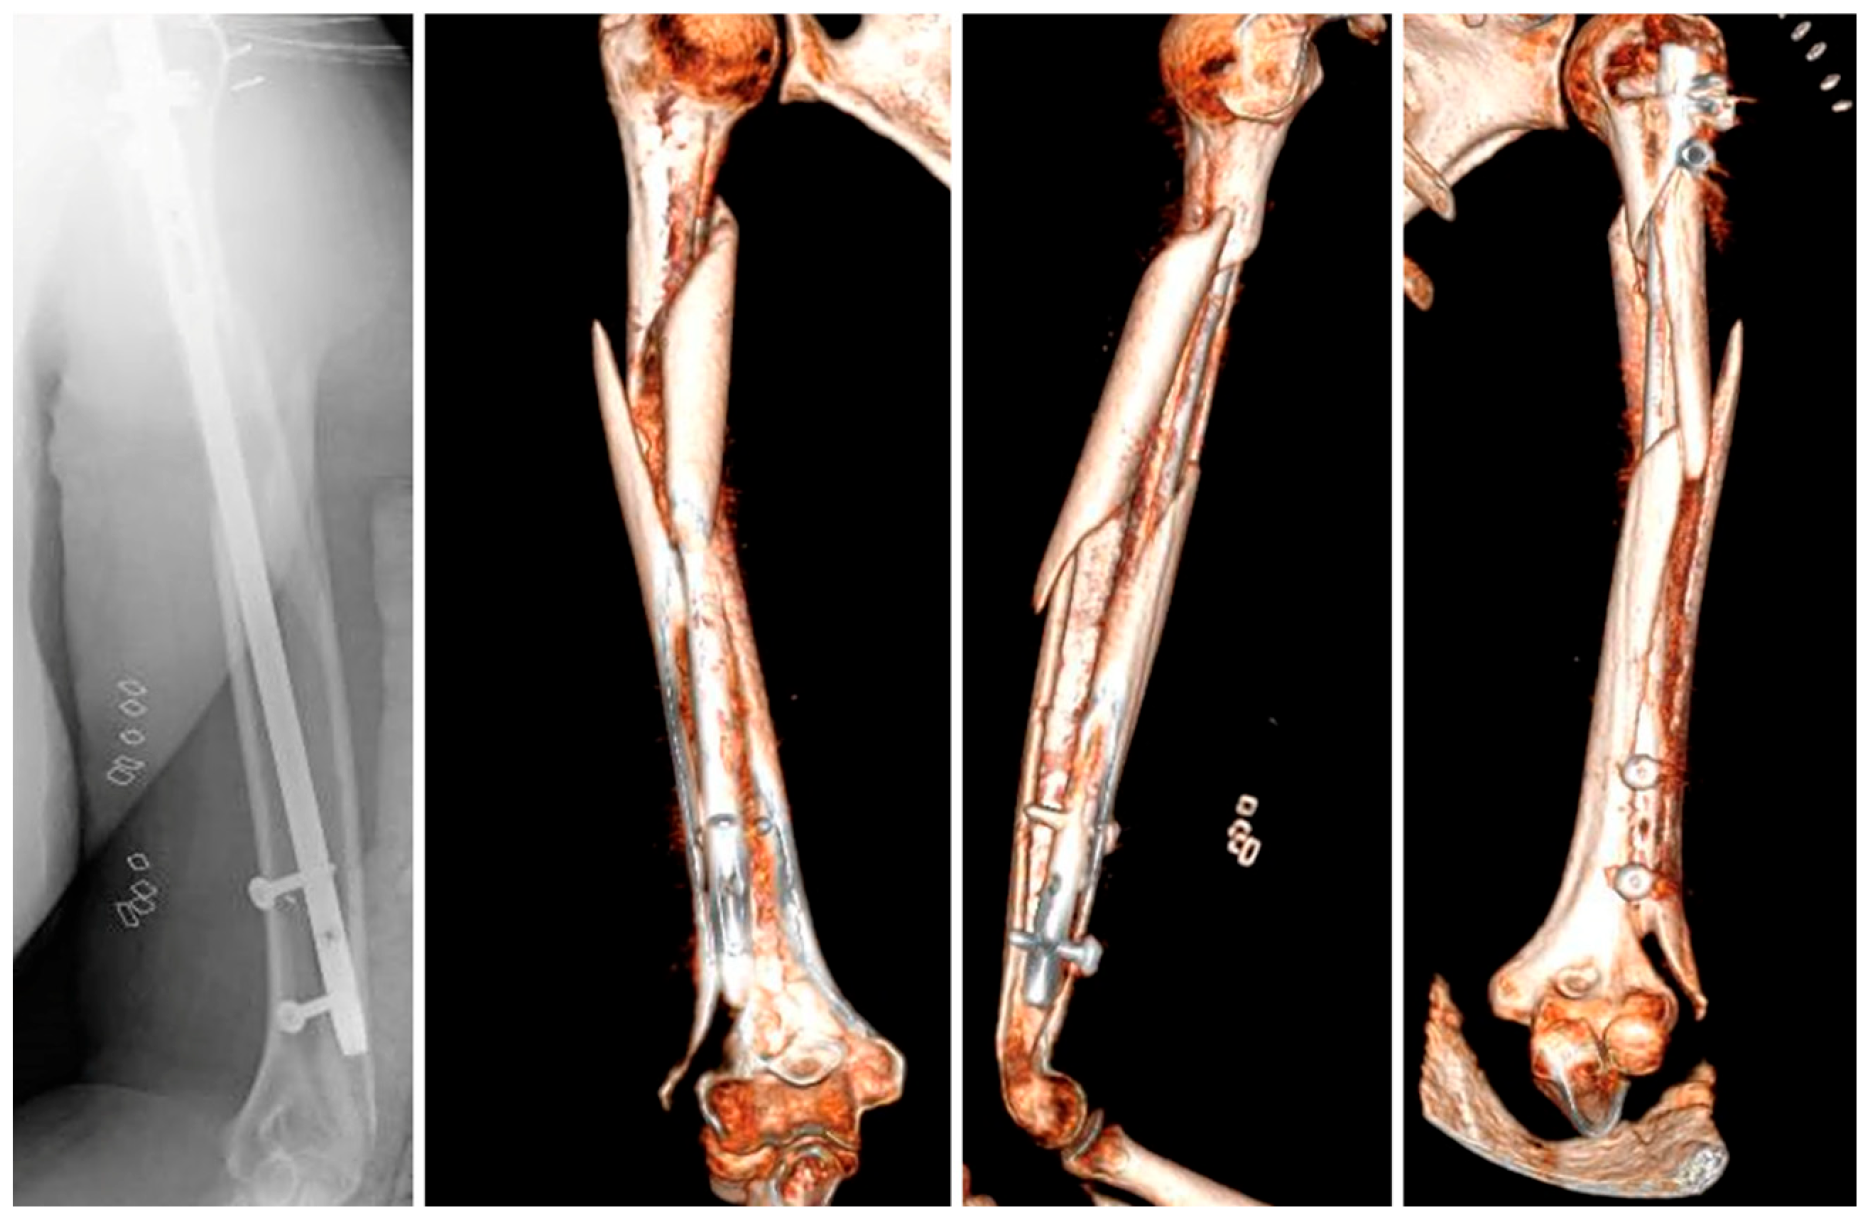

After an initial assessment, a closed reduction was performed followed by placement of an antegrade intramedullary nail. Although there were no issues related to the diameter or curvature of the nail used, a peri-implant fracture occurred at the level of the distal interlocking screw during its insertion, as confirmed by intraoperative fluoroscopy (Figure 2). A decision was made to put an end to the procedure and perform an axial CT-scan to evaluate the morphology of the fracture.

The CT images exhibited a complex fracture originating at the lateral humeral condyle and extending sagittally towards the proximal humerus where it joined the primary spiral fracture, involving the whole of the humeral shaft. Based on this information, it was decided to perform an open reduction and internal fixation of the fracture, using a distal lateral plate combined with a proximal helical plate to ensure a stable fixation.

Figure 2. X-ray and 3D reconstruction of the peri-implant fracture.